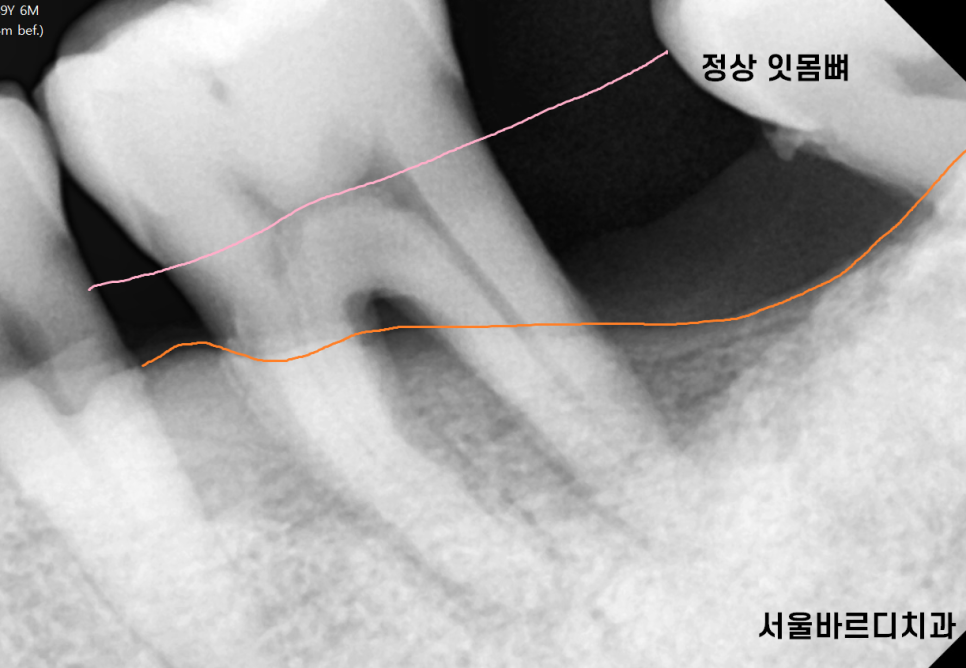

잇몸 무너짐은 잇몸뼈가 내려가는 현상을 뜻합니다.

잇몸이 치아를 제대로 지탱하지 못하고 내려앉는것이죠.

치주질환으로 인해 발생하며 잇몸이 내려가면서

치아가 흔들리는 현상으로 이어질 수 있습니다 .

문제는 약을 먹는다고 내려간 잇몸이 차오르지를 않아요!!

무엇보다도 조기 발견과 치료가 중요해요

잇몸에 문제가 생기면 약으로도 재생되지 않고

잇몸치료를 진행하거나

관리를 아무리 잘해주셔도 재생시켜주지는 못합니다.

단지 더 파괴되는 것을 막아줄 뿐이죠!!